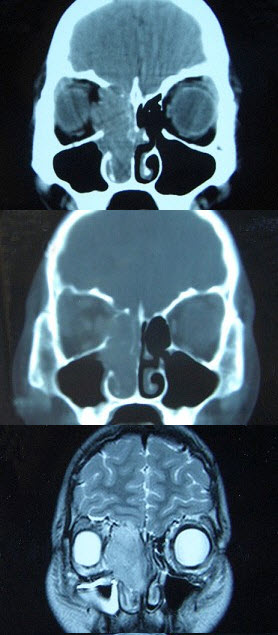

女,16岁,鼻塞、流涕一年余,失去嗅觉,影像检查如图所示,最可能的诊断是()。

A、鼻腔乳头状瘤

B、筛窦癌

C、恶性淋巴瘤

D、小唾液腺癌

E、嗅神经母细胞瘤

E